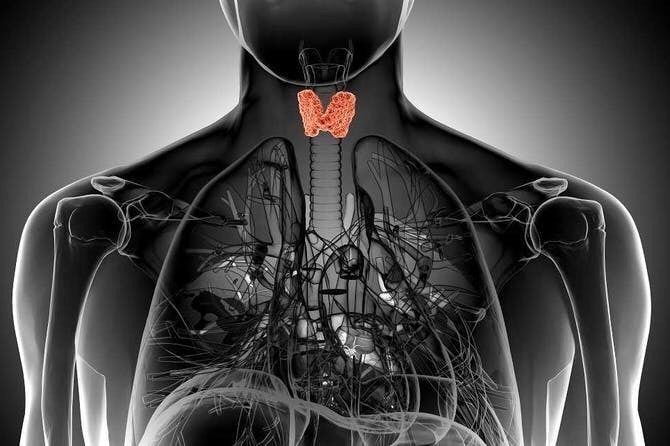

جمهورية مصر تستضيف النسخة الثالثة من المؤتمر الدولي للغدة الدرقية

تنظم الجمعية المصرية للغدة الدرقية، التابعة لوزارة التضامن الاجتماعى، المؤتمر الدولي الثالث، بالتعاون مع الجمعية العربيه للغدة الدرقية.

وتجدر الإشارة إلى أنه من المقرر أن يناقش المؤتمر كل ما يتعلق بالغدة الدرقية، وما طرأ من أبحاث ودراسات فى هذا الصدد، وذلك في إطار الحرص على الكشف المبكر عن التقزم في أطفال المدارس، حيث يستضيف المؤتمر خبراء في مجال التقزم في الأطفال وعلى مدار جلسة كاملة يتم تناول علاقة اضطرابات الغدة الدرقية بتأخر النمو وتأخر البلوغ.

وانطلاقا مما سلف سوف يخصص المؤتمر جلسة كاملة عن علاقة اضطرابات الغدة الدرقية وطرق العلاج، إضافة إلى تأثير إضطرابات الغدة الدرقية وكيفية التشخيص والعلاج.

ونظرا لزيادة معدل انتشار سرطان الغدة الدرقية وما له من تأثير على حياة الفرد يستضيف المؤتمر الدولي جلسة كاملة عن سرطان الغدة الدرقية وأحدث طرق التشخيص والعلاج، كما سيتم تسليط الضوء عن كيفية تشخيص وعلاج حالات طوارئ الغدة الدرقية وكذلك الأمراض النادرة التي تصيب الغدة الدرقية ويصعب تشخيصها ومعرفتها.

وبناء على ذلك يوضح المؤتمر كيفية استخدام التقنيات الحديثة في الجراحة وكيفية استئصال الغدة الدرقية بالمنظار، من خلال ورشة عمل استثنائية.